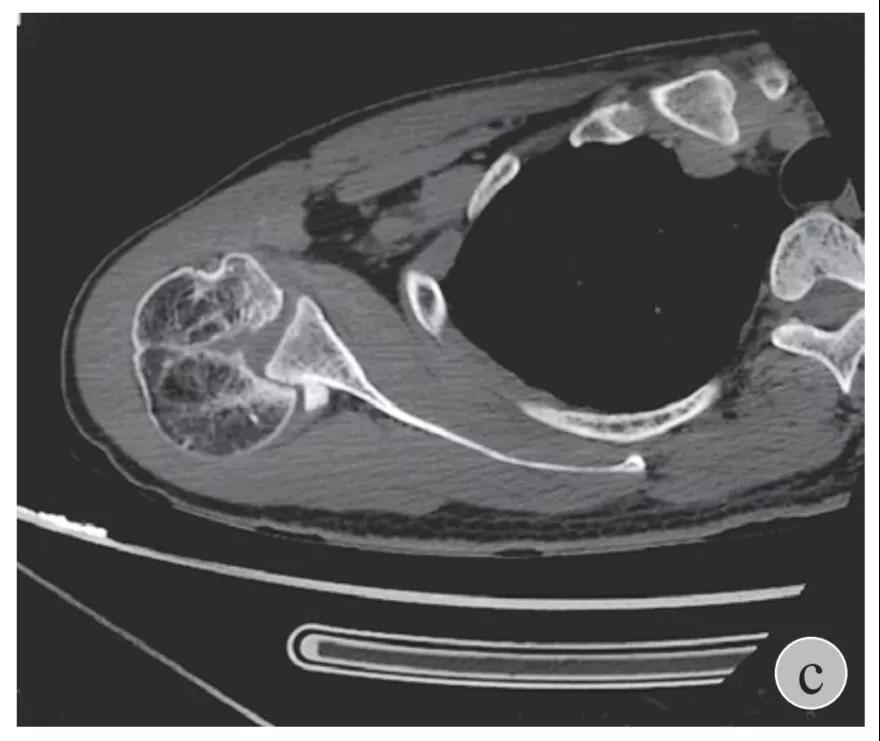

就诊我院后完善CT,诊断明确——左肩关节后脱位:

予以手法复位后拍片复查显示“灯泡征”消失,复位成功。讨论:肩关节后脱位在临床较为少见,特别是影像科经验不足很容易漏报,所以我们临床医生一定要自己仔细阅片,同时要结合体查来进行诊断,防止漏诊。肩关节后脱位时体查也有明显特征:肩关节前方明显变平,喙突较平时明显凸起容易触及,而肩关节后方明显丰满,上臂一般处于内旋内收位,无法主动外旋外展。肩关节后脱位的手法复位相对于前脱位的复位来说也比较容易。患者一般可以取坐位,助手自患侧腋下环抱患者稳定患者躯体,术者一手拉患肢上臂稍牵引内旋,一手自后方推顶肱骨头一般可以复位,如果单纯推顶无法复位也可以术者两手握住伤肢缓慢外展并沿肱骨纵轴牵引,然后逐渐外旋上臂即可复位。整复完成后可以把持患肢作肩关节各个方向的小幅度被动活动,防止肩关节粘连,肩关节后脱位的固定方法与肩关节前脱位的固定方法不同,应将患肢置于上臂外展、后伸、外旋位固定,即外展30度、后伸30度和轻度外旋位,用外展支架固定3周后,循序渐进开始肩关节功能康复。